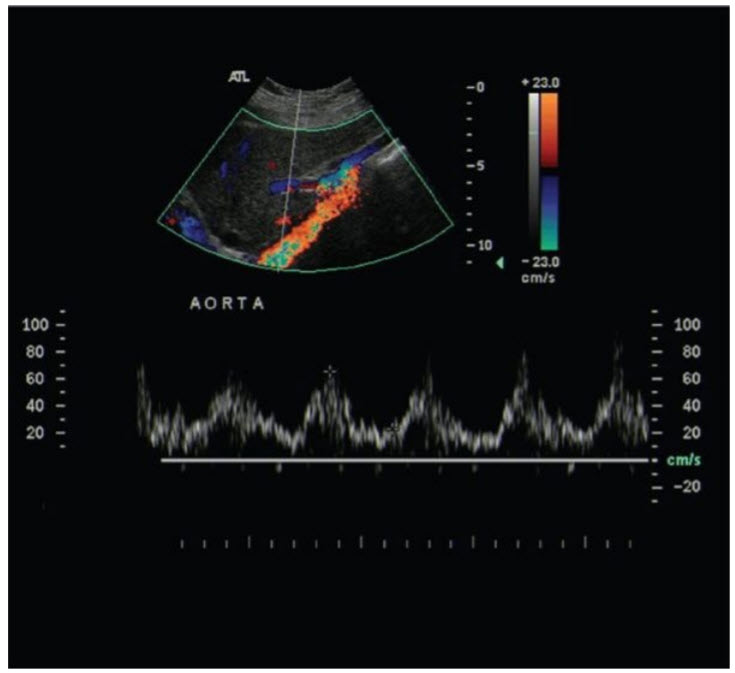

Which of the following statements is correct regarding the echocardiographic image from this patient obtained from the abdominal aorta (figure below).

A. The hallmark of coarctation is the presence of low systolic velocities

B. The presence of coarctation cannot be determined without knowing the timing of the pulse delay relative to aortic ejection

C. The hallmark of coarctation is the presence of persistent antegrade flow in diastole

D. The presence of coarctation cannot be determined without additional Doppler images proximal to the coarctation site